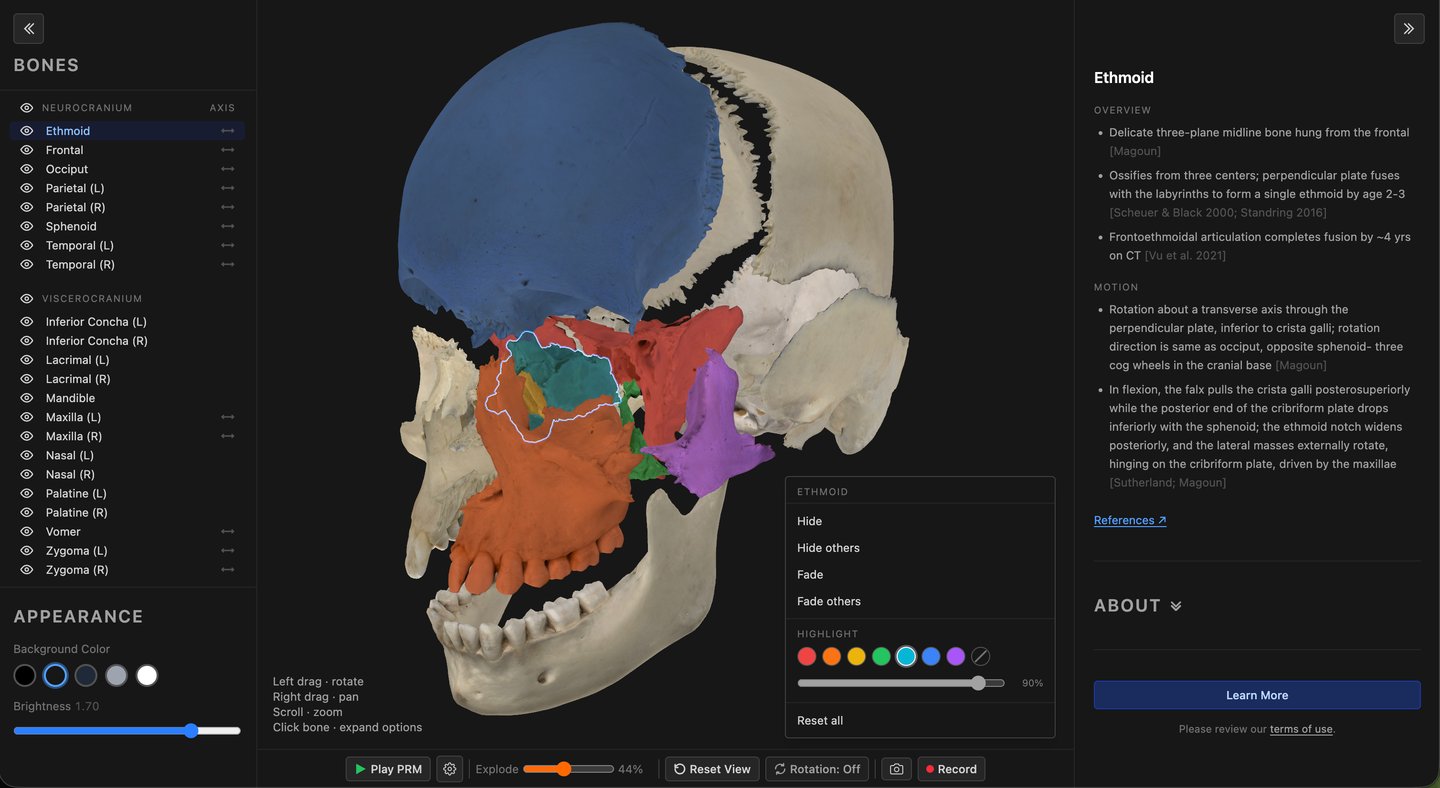

CranialLab is a free 3D cranial anatomy atlas. Each model is built from photogrammetry of real human bone — not synthetic renders — giving students and educators an accurate, interactive reference for cranial anatomy, suture relationships, and the anatomical basis of primary respiratory motion.